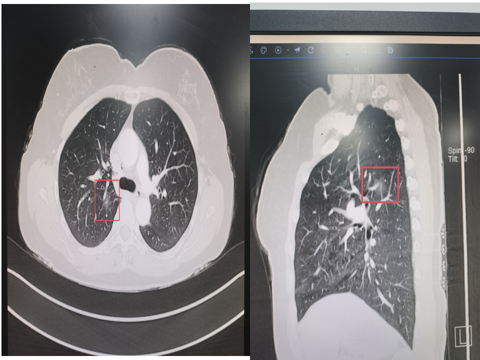

曾有一位女性患者,在 4 个月前于我院进行体检时,胸部 CT 检查发现了右肺结节,随后以 “肺结节” 被收入我科住院治疗。

胸部CT:右肺上叶后段磨玻璃结节(1.4cm*0.6cm)

胸部CT:右中肺结节(直径约0.4cm)

胸部三维重建

广州医科大学(国家呼吸中心)的崔飞教授仔细阅片后,综合各项因素,考虑该结节为早期肺癌的可能性较大,建议患者接受手术治疗。

在术前,医疗团队运用 CT 引导技术,对结节进行了精准定位,为手术的顺利开展奠定了坚实基础。术中,结合三维重建技术,医生成功实施了精准肺联合亚段切除手术。整个手术过程仅耗时 1 个半小时,便顺利完成,充分展现了医疗团队的精湛技术与先进设备的完美结合。